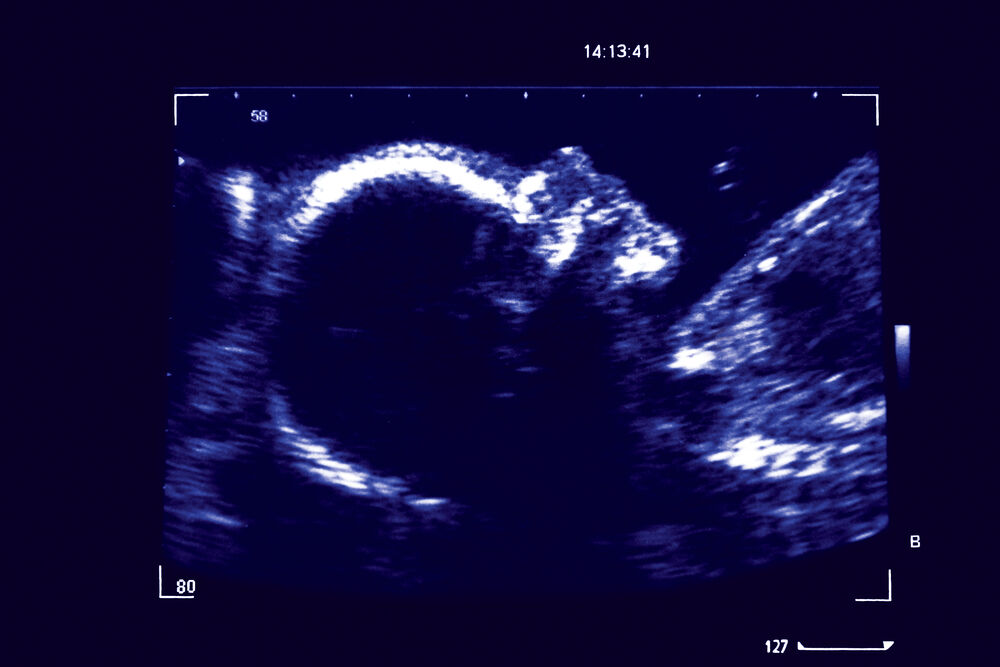

baby at 14 weeks 2 days ultrasound

Read our true stories. 14 week Ultrasound can be performed Transabdominally or Transvaginally and. The first ultrasound done between 10 and 14 weeks is considered the most.

14 Weeks Pregnant Ultrasound Procedure Abnormalities And More

Pregnancy Ultrasound 14 Weeks Centromere S Churva